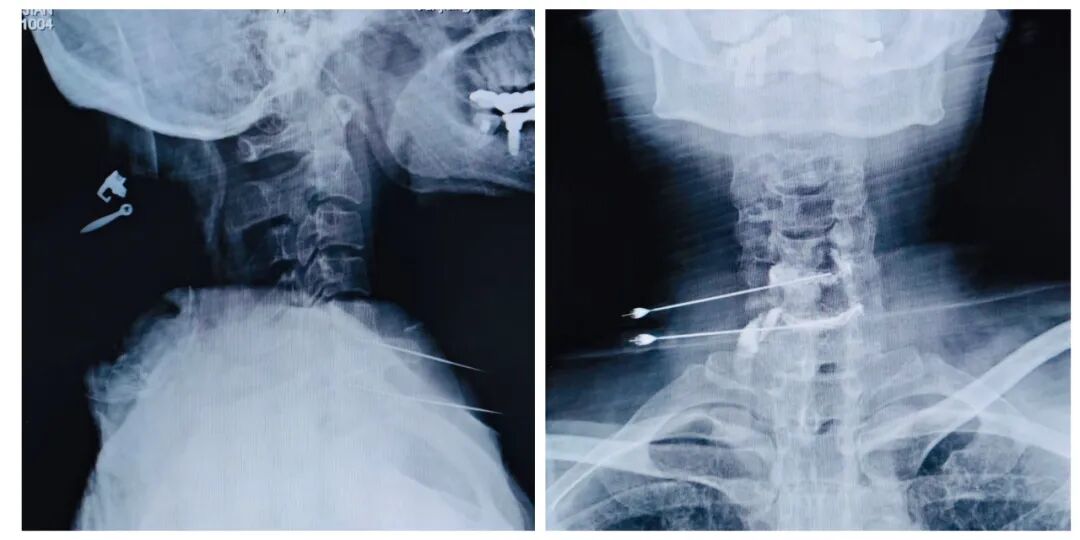

图片说明:术中穿刺影像